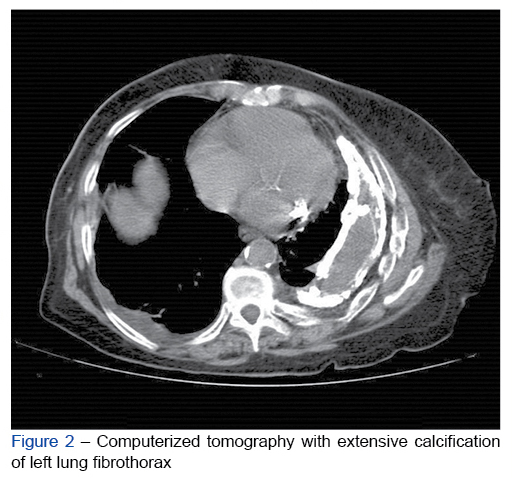

A 91-year-old woman presented with a 2-week history of dyspnea and productive cough. She was autonomous regarding the activities of daily living and had a medical hist...